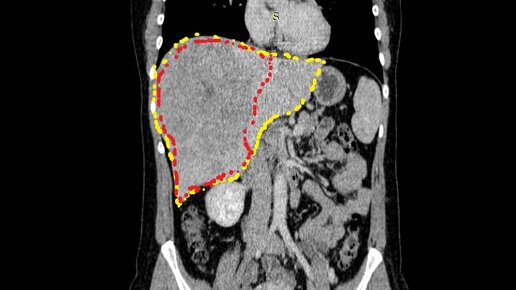

История пациентки И., 40 лет. Около 2 лет назад впервые появились жалобы на тупого характера ноющую боль в правом подреберье. Как свойственно людям молодого возраста, особого значения боли И. не придавала, мыслей о плохом не было, поэтому за медицинской помощью не обращалась почти полгода. Но боль не проходила, а со временем даже стала усиливаться. При обследовании по месту жительства выявлено объемное образование печени больших размеров (150х120х160 мм), вторичноочаговое поражение наддиафрагмальных лимфоузлов...